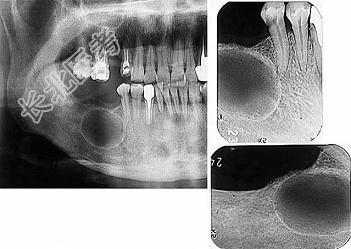

- 单项选择题发现下前牙变色,唇侧牙龈一肿物一月余, 经X 线检查,结果如图。最可能的诊断是 ( )

A、根尖囊肿

B、牙龈瘤

C、根尖脓肿

D、成釉细胞瘤

E、牙骨质瘤